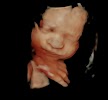

Barefoot Babies

105 Roxie Ave, Fayetteville, NC 28304, United States

Had my 2D/3D ultrasound today and the experience was great! From the moment I booked my appointment to moment I walked into the ultrasound room. Paige was awesome she was informative, sweet and helpful. Lesa the tech was absolutely great and she took her time. Definitely, worth it I’ll be back in January for my 4D ultrasound! Thank you guys!!!

2 Photos